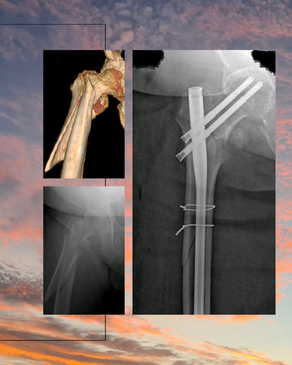

Dr. Rodrigo Aguirre Rojas is the best Orthopedic Surgeon in San Jose del Cabo, Mexico. Book your consultation for Hip and Knee Replacements in Los Cabos, Mexico at PlacidWay. Emergencies like Fractures and Dislocations are also evaluated and treated